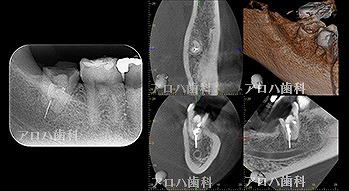

case10

左上に腫脹、圧痛

根尖部に透過像

術前、術直後、予後

術前、術後